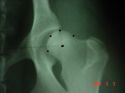

Kattintás=nagyításSúlyos dysplasiánál a combcsontfej deformált, luxált illetve subluxált (90° alatti), az ízületi rés tág, erősen divergáló, a vápa lapos, az ízületben illetve környékén arthroticus elváltozások lehetnek.